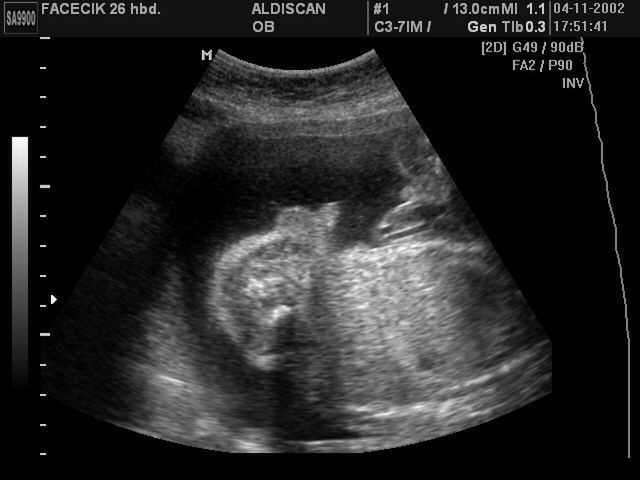

Płód w 26 tygodniu ciąży, na zdjęciu widoczne męskie narządy płciowe

/ 10Zdjęcia płodu - męskie narządy płciowe